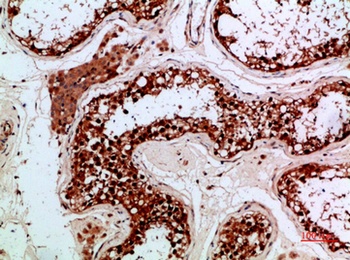

Immunohistochemical analysis of PENK staining in human testis formalin fixed paraffin embedded tissue section. The section was pre-treated using heat mediated antigen retrieval with sodium citrate buffer (pH 6.0). The section was then incubated with the antibody at room temperature and detected using an HRP conjugated compact polymer system. DAB was used as the chromogen. The section was then counterstained with haematoxylin and mounted with DPX.